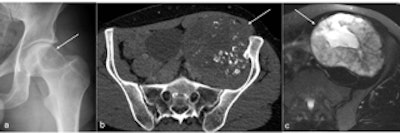

Clear cell chondrosarcoma can be seen in the left femoral head (arrow in a), and chondrosarcoma is visible in the left ilium (arrow in b and c). All figures courtesy of Dr. Rajesh Botchu.